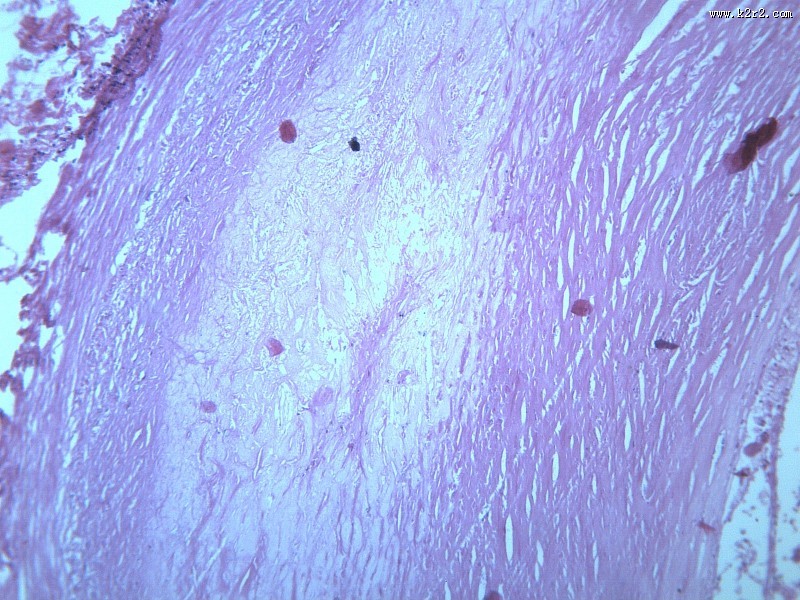

首页 > 其他类别 > 动脉粥样硬化(12张) > 动脉粥样硬化 第6张

动脉粥样硬化 - 第6张